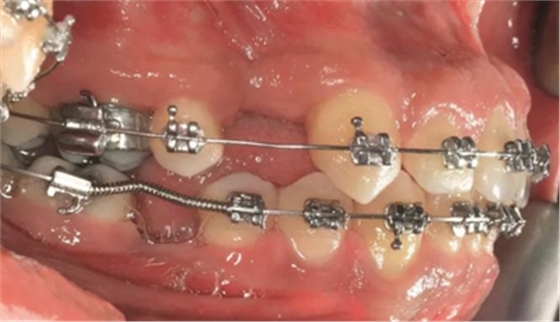

圖5a. 病例2中右下第一磨牙加速種植位點(diǎn)改建。初期排齊期間

圖5h. 通過(guò)帶有一個(gè)后傾彎的鋼絲以及開(kāi)放彈簧的半托槽距離輕加力實(shí)現(xiàn)了生物力學(xué)直立磨牙